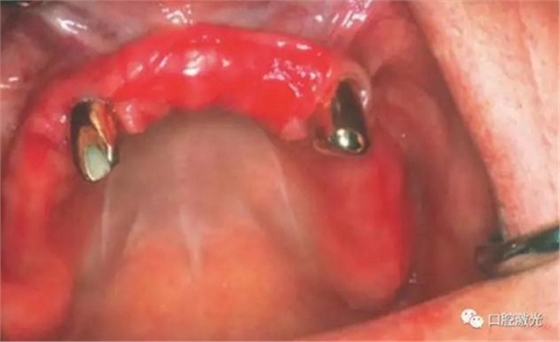

患者女性,43歲。在18年前在13位置上安裝種植體。整個(gè)上顎除23外,牙盡缺失。安裝種植體后,在種植體及23上固定套筒冠義齒。3年后患者發(fā)現(xiàn)刷牙時(shí),臨近13有大量出血現(xiàn)象。通過(guò)探針檢查發(fā)現(xiàn)深度達(dá)6mm。

如今,種植體周圍炎的治療完成已經(jīng)過(guò)去了10多年,上顎義齒的狀況沒(méi)有再出現(xiàn)問(wèn)題。種植體周圍組織基本健康。